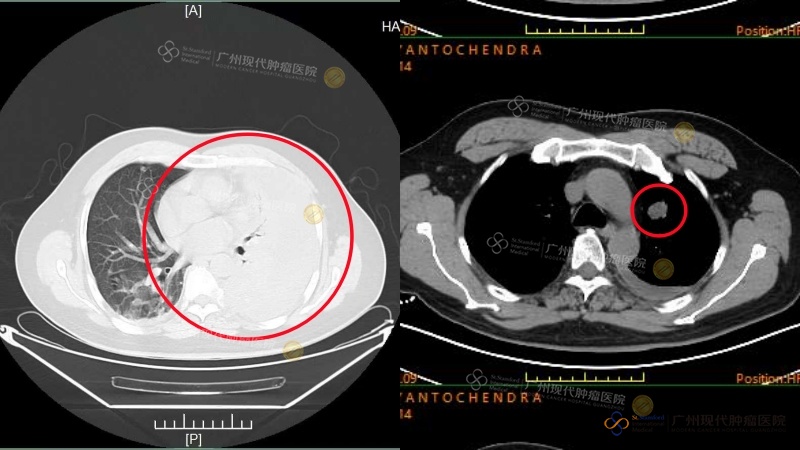

Perbandingan CT Scan sebelum dan sesudah pengobatan Ny. Lin

Seorang pasien kanker payudara asal Indonesia, Ny. Lin (nama samaran), yang ditangani oleh Prof. Dai, secara tak terduga mendapati adanya tumor payudara saat menjalani pemeriksaan kesehatan rutin. Saat diagnosis awal, penyakitnya telah menyebar ke kelenjar getah bening aksila dan tulang, bahkan menyebabkan penekanan pada sumsum tulang belakang, yang hampir membuatnya mengalami kelumpuhan. Setelah dilakukan diskusi dan evaluasi oleh tim MDT dari Modern Cancer Hospital Guangzhou, dirumuskan rencana pengobatan individual berupa “operasi tulang belakang yang dikombinasikan dengan terapi endokrin sistemik”. Sejak memulai pengobatan pada Agustus 2024 hingga saat ini, hasil evaluasi menunjukkan bahwa tumor dalam tubuh Ny. Lin telah mencapai status PR (Partial Response), yaitu penyusutan tumor lebih dari 50%. Kekuatan otot pada kedua tungkai bawahnya telah pulih sepenuhnya, kualitas hidupnya meningkat secara signifikan, dan ia berhasil terhindar dari risiko kelumpuhan.